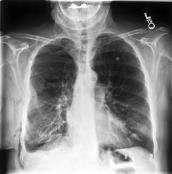

Large numbers of labeled medical images are essential for the accurate detection of anomalies, but manual annotation is labor-intensive and time-consuming. Self-supervised learning (SSL) is a training method to learn data-specific features without manual annotation. Several SSL-based models have been employed in medical image anomaly detection. These SSL methods effectively learn representations in several field-specific images, such as natural and industrial product images. However, owing to the requirement of medical expertise, typical SSL-based models are inefficient in medical image anomaly detection. We present an SSL-based model that enables anatomical structure-based unsupervised anomaly detection (UAD). The model employs the anatomy-aware pasting (AnatPaste) augmentation tool. AnatPaste employs a threshold-based lung segmentation pretext task to create anomalies in normal chest radiographs, which are used for model pretraining. These anomalies are similar to real anomalies and help the model recognize them. We evaluate our model on three opensource chest radiograph datasets. Our model exhibit area under curves (AUC) of 92.1%, 78.7%, and 81.9%, which are the highest among existing UAD models. This is the first SSL model to employ anatomical information as a pretext task. AnatPaste can be applied in various deep learning models and downstream tasks. It can be employed for other modalities by fixing appropriate segmentation. Our code is publicly available at: https://github.com/jun-sato/AnatPaste.